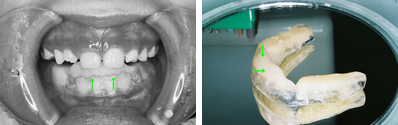

前歯の反対咬合と凸凹を解消した8歳

前歯の反対咬合と、それに合せて歯肉が下がっていることが心配されました。下顎の凸凹も問題でした。

上顎左側の2番目の永久歯(側切歯)が反対咬合です。まだ乳歯も多く残る歯並びですが、全体に凸凹が認められます。